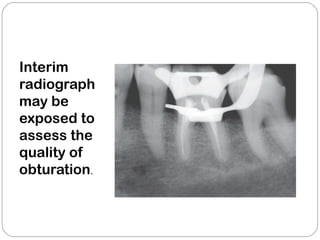

Interim

radiograph

may be

exposed to

assess the

quality of

obturation.